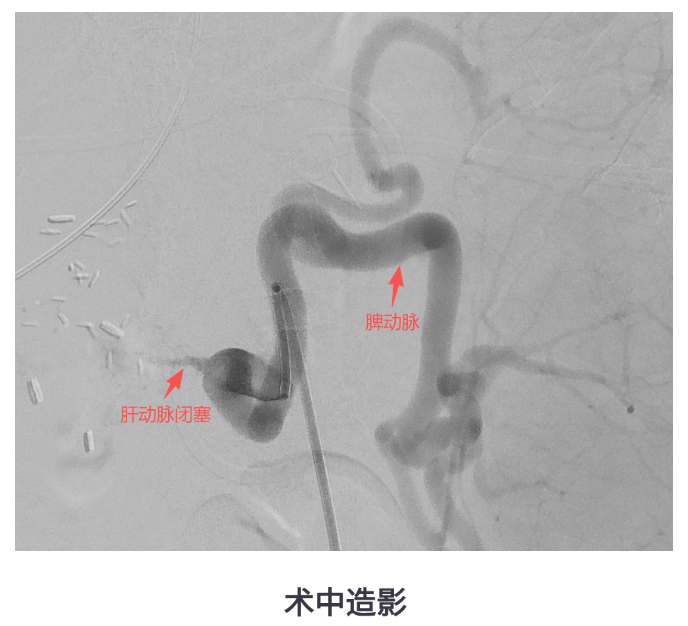

转入我院后,CT显示患者肝脏包膜下积气、肝右叶低密度影,提示脓肿复发,同时存在门静脉高压、脾大、肝动脉狭窄等复杂情况。医疗团队决定为她实施经导管脾动脉栓塞术(SAE),并同期进行肝动脉造影和压力测量。

术后,王女士的门静脉压力从术前的较高水平明显下降,肝动脉血流改善,发热控制,病情稳步好转。SAE不仅缓解了脾功能亢进,还间接改善了患者的肝动脉供血,为控制脓肿创造了有利条件。

脾动脉栓塞是一种介入微创手术,通过堵塞部分脾动脉血流,减少脾脏对门静脉系统的“输血量”,从而降低门静脉压力,改善肝动脉灌注。近年多项研究表明,SAE能显著改善肝动脉阻力指数,提升肝动脉血流,对治疗门静脉高灌注、顽固性腹水、肝脓肿等并发症安全有效。